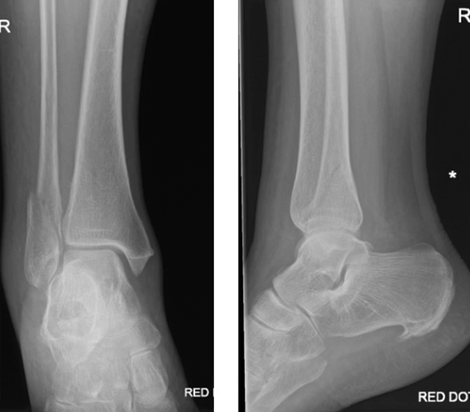

What is shown in this X-ray?

A

Weber’s A fracture

Weber’s B fracture

Weber’s C fracture with medial malleolus fracture